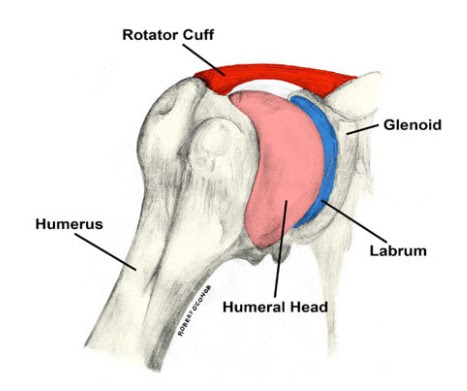

Glenoid Labrum

Glenohumeral ligament